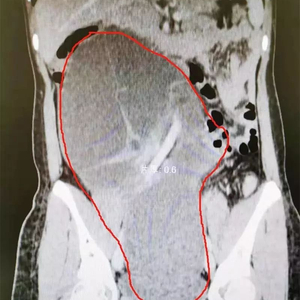

红色边框圈住处为囊肿。

不查不知道,一查吓一跳。据检查,在林小姐的右侧卵巢内,长了一个大小约18.1x9.8x31厘米的巨大卵巢囊腺瘤。“像篮球一样大,占据了整个盆腹腔。”广东医科大学顺德妇女儿童医院妇科副主任温国群称,由于肿瘤异常巨大,整个肚子几乎都被撑满,因此有破裂的危险。

“从腹腔镜看到,林小姐腹腔内的巨大肿瘤已达肝脏下缘,充满盆腹腔,能做腹腔镜微创手术非常不容易。”温国群表示,因为林小姐体内的肿瘤太大,手术操作起来非常困难,稍有不慎,不但无法取出囊肿,腹腔镜手术器械还极易伤及周围其他的器官组织,造成无法想象的后果。